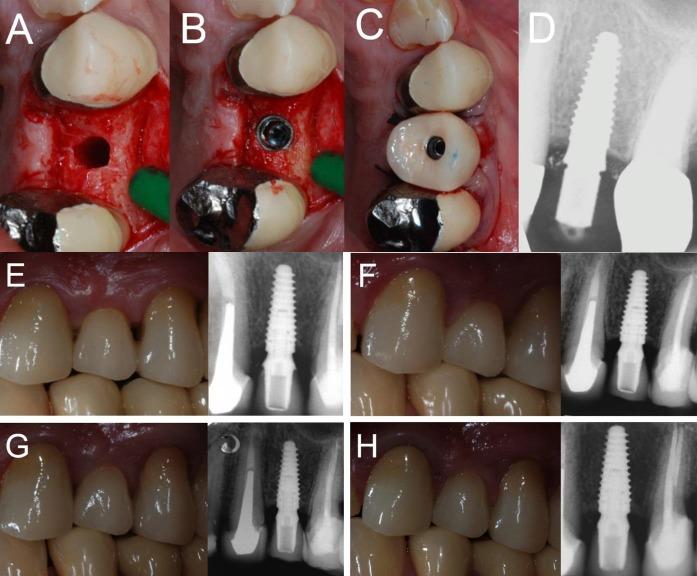

在当前的科学文献中,关于单个种植体即刻功能负载的研究很少。本研究的目的是评估植入愈合牙槽嵴和新鲜拔牙位点的即刻负载单个种植体的4年生存率、并发症发生率和种植体周围边缘骨吸收(PIMBL)情况。六个中心参与了这项前瞻性研究。在开始招募患者之前,详细定义了手术和修复方案。患者招募和手术于2012年2月至2013年2月期间进行。纳入标准为愈合牙槽嵴和新鲜拔牙窝中的单牙间隙。所有种植体(Anyridge®,韩国庆尚北道Megagen公司)在植入后即刻进行功能负载,并随访4年。观察指标为种植体生存率、并发症和PIMBL。选择了46例患者(年龄18 - 73岁)。总共植入了57颗种植体(10颗植入新鲜拔牙窝)。经过4年的功能负载,仅一颗种植体丢失;因此,报告了较高的生存率(基于患者为97.6%;基于种植体为98.1%)。此外,报告的生物学并发症(基于患者为4.8%;基于种植体为3.8%)和修复并发症(基于患者为9.7%;基于种植体为7.6%)发生率有限。4年总的PIMBL为0.38±0.21 mm(愈合牙槽嵴:0.4±0.21 mm;新鲜拔牙窝:0.33±0.20 mm)。即刻负载单个种植体似乎是一种非常成功的治疗方式。然而,需要长期数据来证实这些积极结果。

https://cdn.ncbi.nlm.nih.gov/pmc/blobs/87a2/5928471/e3b97f58994e/joddd-12-26-g004.jpg

https://cdn.ncbi.nlm.nih.gov/pmc/blobs/87a2/5928471/e952139cd01e/joddd-12-26-g001.jpg

https://cdn.ncbi.nlm.nih.gov/pmc/blobs/87a2/5928471/7ba5040a8f0a/joddd-12-26-g002.jpg

https://cdn.ncbi.nlm.nih.gov/pmc/blobs/87a2/5928471/21c584e33dfc/joddd-12-26-g003.jpg